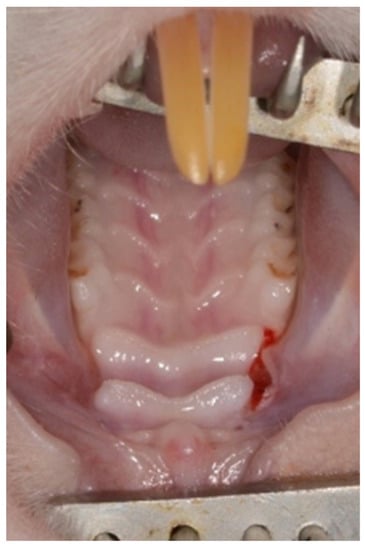

General anesthesia was achieved by an intraperitoneal injection of 0.1% Xylazine (10 mg/kg) and 0.1% Ketamine (80 mg/kg). In addition, Isoflurane (TerrellTM) was administered by a vaporizer at 2%–3% 100–200 mL/min combined with oxygen supply. Local anesthesia was performed using 0.4 mL Lidocaine 0.5% with adrenaline 1:100,000. A palatal incision was made on the maxillary alveolar ridge in the existing edentulous area between the 1st molar and the incisors using a 15c blade (Figure 1).

Figure 1. Palatal incision.